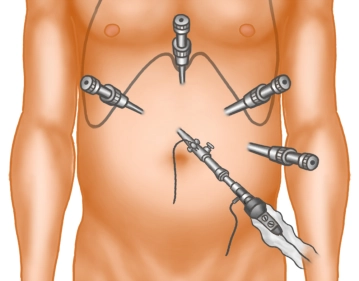

Trokarpositionierung